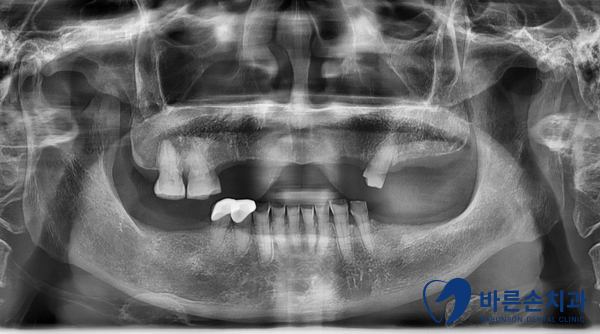

Before 25.03.26

위에는 틀니를 사용중 이시고,

아래는 어금니가 없기도 한데,

전체적으로 치아가 많이 마모가 되어서

치아가 점점 짧아지니 개선하고 싶어 하셨습니다.

상실된 어금니는 임플란트 식립하고

짧아진 치아들은 지르코니아 보철치료를 해서

개선하기로 결정하였습니다.